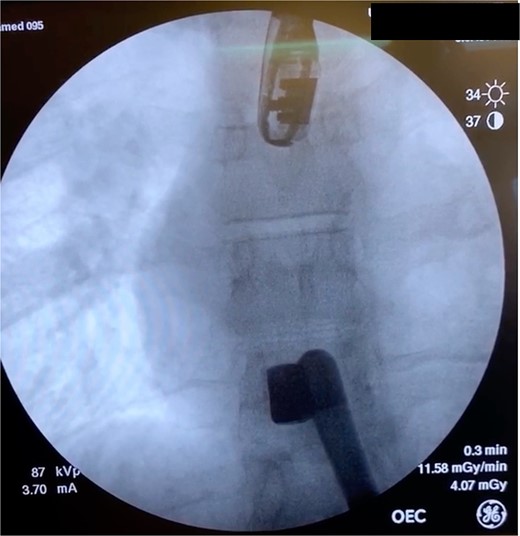

On hospital Day 7, the patient had acute hypoxic respiratory failure. CT chest found a right segmental pulmonary embolism and a retained bullet near the aortic root. A TEE was repeated, this time demonstrating severe aortic insufficiency (Fig. 4), and a bullet in the left coronary cusp. Cardiothoracic surgery was consulted for evaluation and management. The next day, the patient went to the OR for median sternotomy, cardiopulmonary bypass, aortic root repair with patch, re-attachment of the left coronary cusp, and removal of the bullet from the aortic root.

TEE with intracardiac bullet, severe aortic insufficiency. The bullet is labeled by an asterisk, with shadow artifact posterior to the bullet.

Case 2 involved a hemodynamically unstable patient with multiple thoracoabdominal GSWs. The surgical team identified six GSWs and five retained bullets. The patient’s instability precluded CT imaging. A cardiac injury was suspected due to a bullet overlying the cardiac silhouette and significant chest tube output. Thoracotomy confirmed a cardiac injury with tamponade, necessitating immediate repair. The bullet trajectory suggested it passed through the heart and diaphragm into the abdomen. TEE revealed no intracardiac shunting, valve insufficiency, or bullet. The bullet injured the left ventricle and embolized to the aortic root, becoming symptomatic on hospital Day 7. A CT scan suggested an intravascular bullet near the aortic valve, confirmed by TEE showing severe aortic insufficiency. The patient required four operations for definitive management. This case underscores the risks of conservative management and the need for thorough evaluation in unstable patients.